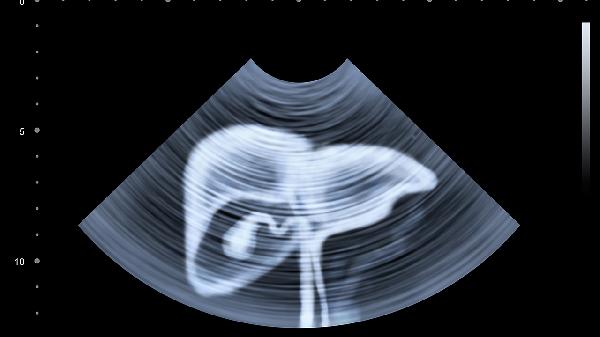

預防丙肝需要采取避免血液暴露、規(guī)范醫(yī)療操作、注意個人衛(wèi)生、避免高危行為、定期篩查等措施。丙型肝炎病毒主要通過血液傳播,采取針對性防護可有效降低感染風險。

醫(yī)療機構須嚴格執(zhí)行消毒規(guī)范,使用一次性醫(yī)療器械。血液制品需經(jīng)過丙肝病毒核酸檢測,器官移植前需進行供體篩查。內(nèi)鏡檢查、血液透析等侵入性操作應落實標準預防措施。